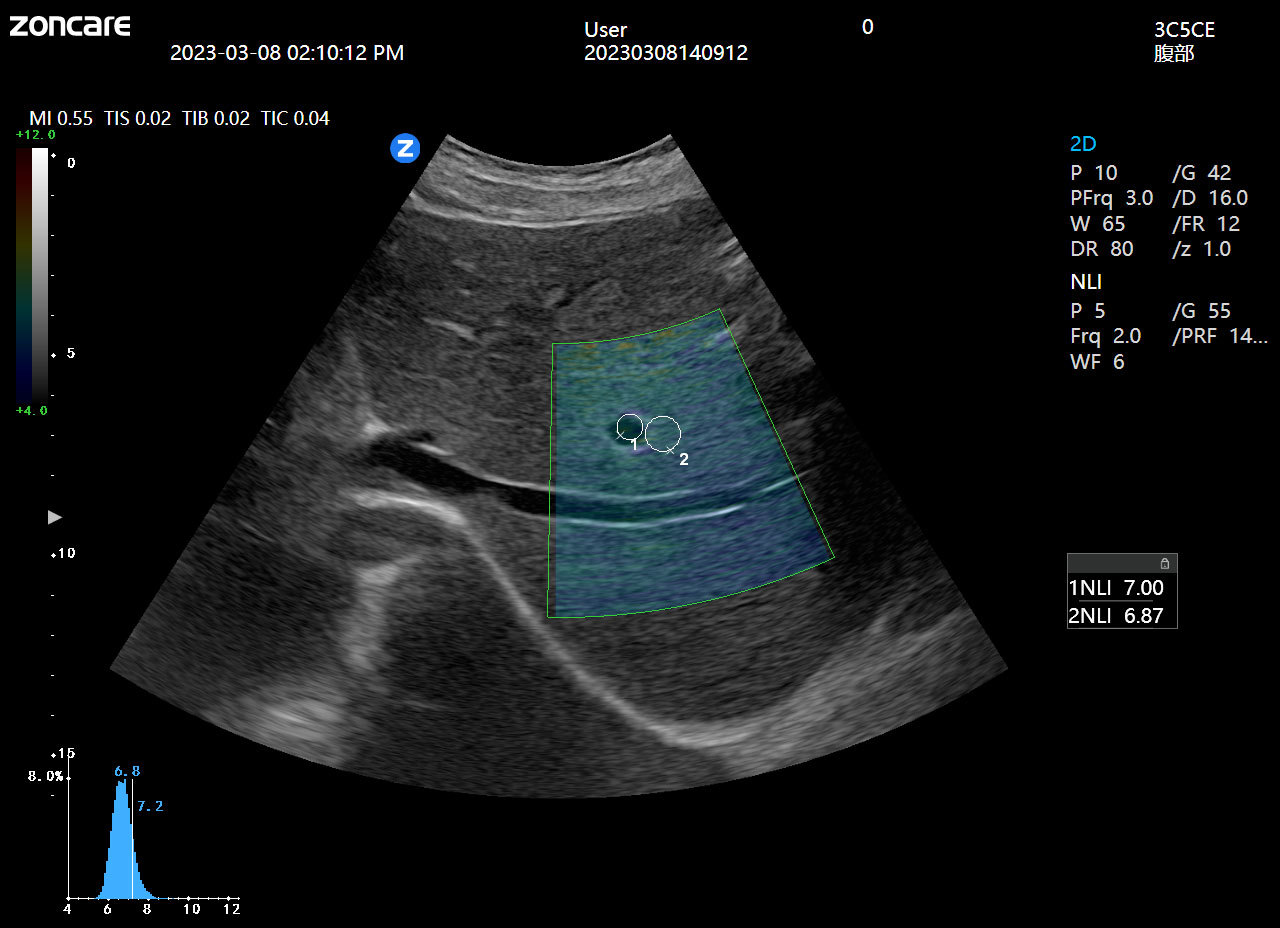

非线性参数成像

可对组织内部非线性参数进行定量成像,对肝病鉴别具有良好的临床应用价值